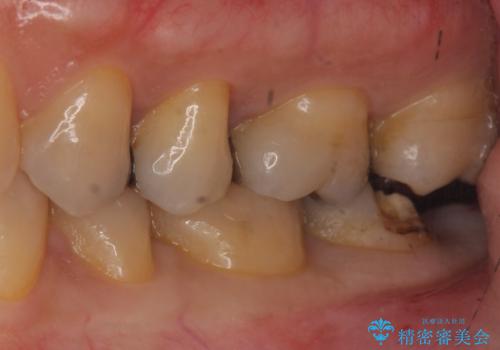

- 銀の詰め物が取れたとのことで来院。

詰め物の下には虫歯がありました。

銀の詰め物はかなり昔に治療されたそうです。

銀の詰め物は虫歯の再発リスクが高く、歯に痛みが出てしまうと歯の神経の治療もしないとならなくなってしまいます。